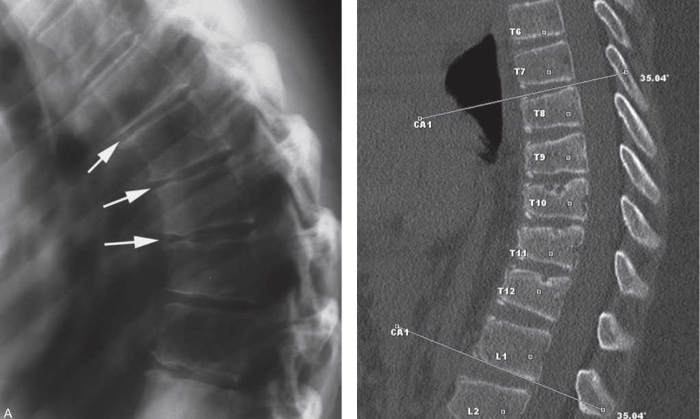

Существует два типа кифоза: физиологический и патологический. В физиологическом варианте угол наклона не превышает 30°. Патологическая форма может быть врожденной или приобретенной. При измерении по методу Кобба угол наклона превышает 30°.

Также назначаются функциональные тесты для определения неврологического статуса пациента и оценки сухожильных рефлексов. Обязательным этапом является рентгенологическое исследование позвоночника, которое может быть выполнено традиционными или альтернативными методами.

Для диагностики сопутствующих заболеваний используется МРТ. Компьютерная томография (КТ) помогает определить степень кифоза и выявить патологические изменения в костных тканях. Могут быть назначены стандартные анализы крови и мочи.